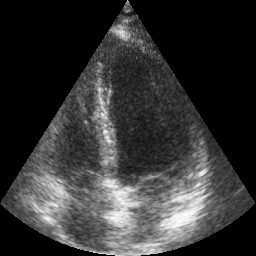

Transthoracic echo is one of the most common means of cardiac studies in the clinical routines. During the echo exam, the sonographer captures a set of standard cross sections (echo views) of the heart. Each 2D echo view cuts through the 3D cardiac geometry via a unique plane. Consequently, different views share some limited information. In this work, we investigate the feasibility of generating a 2D echo view using another view based on adversarial generative models. The objective optimized to train the view-conversion model is based on the ideas introduced by LSGAN, PatchGAN and Conditional GAN (cGAN). The size and length of the left ventricle in the generated target echo view is compared against that of the target ground-truth to assess the validity of the echo view conversion. Results show that there is a correlation of 0.50 between the LV areas and 0.49 between the LV lengths of the generated target frames and the real target frames.